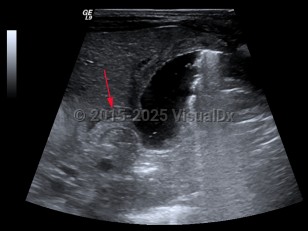

Hypertrophic pyloric stenosis

Hypertrophic pyloric stenosis (PS) is a narrowing of the pyloric lumen due to tissue hypertrophy and scarring. The resultant intestinal narrowing leads to gastric outlet obstruction and bowel obstruction. Although hypertrophic PS can very rarely occur in children and adults, this summary is focused on infantile hypertrophic PS. Patients present with emesis, usually within the first several months of life.

PS is predominantly seen in males (approximately 4:1) and presents typically at 2-7 weeks of life with nonbilious, postprandial projectile emesis and dehydration. Children of parents who had PS have a 20% increased risk of developing PS, suggesting a genetic component, although no clear genetic etiology has been identified.

The complications of PS are due to dehydration and malnutrition. Patients often present with lethargy, failure to thrive, and a hypochloremic, hypokalemic metabolic alkalosis.